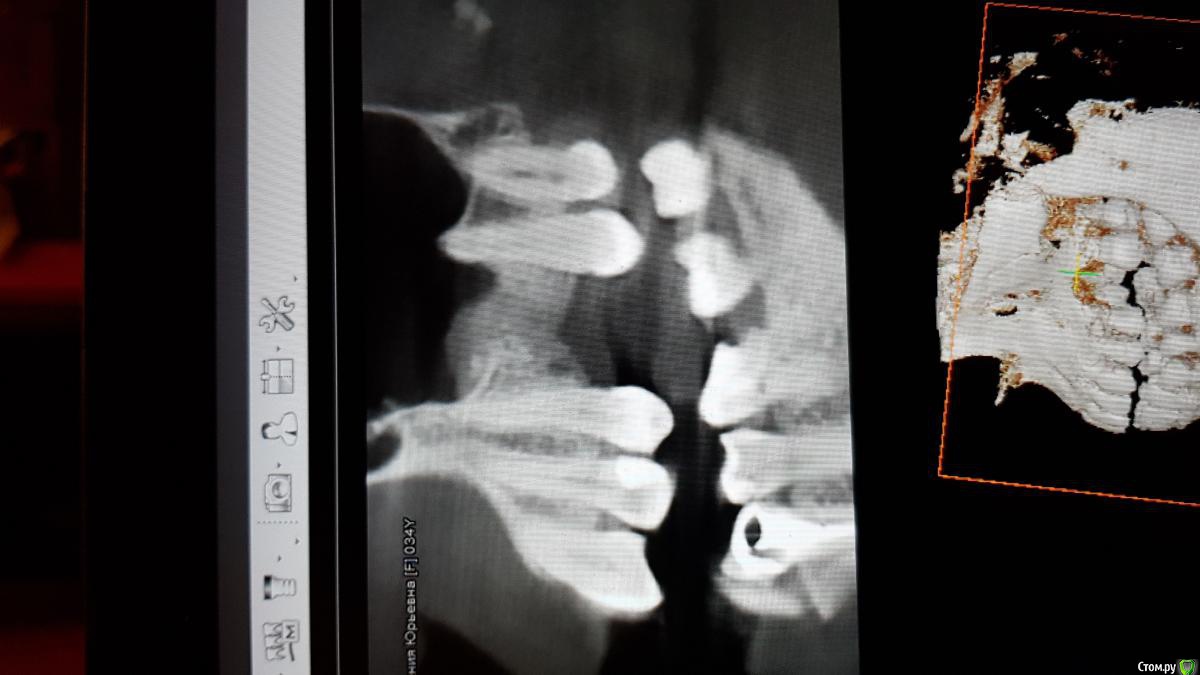

Bier Опубликовано 14 августа, 2018 Поделиться Опубликовано 14 августа, 2018 скорее всего в 1 этап, не вижу особых проблем в пазухе, кроме не заросшей кости в области лунки 2 Ссылка на комментарий

Bier Опубликовано 14 августа, 2018 Поделиться Опубликовано 14 августа, 2018 Если думать о пазухе, то да. Имплантат сразу.Больше смущает кость альвеолярного гребня. 2 Ссылка на комментарий